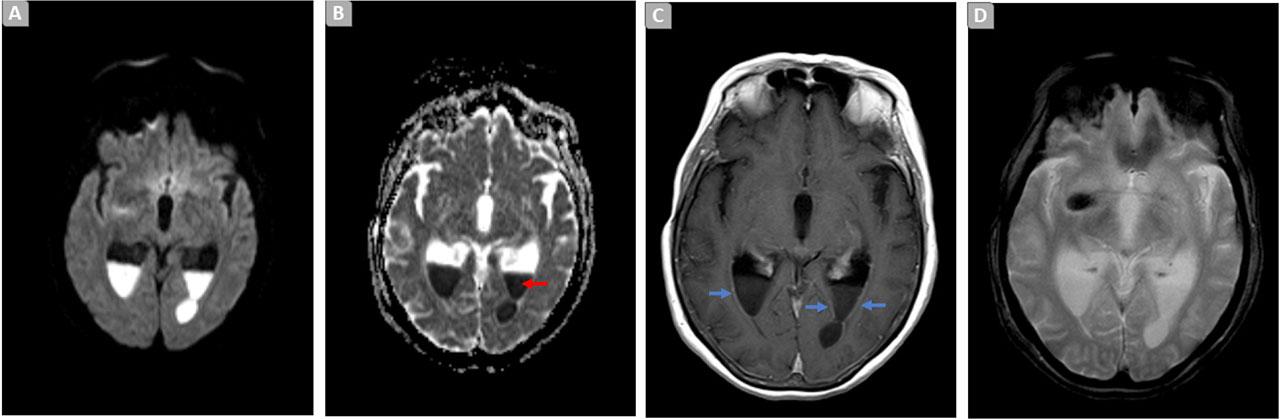

To assess the extent of the central nervous system (CNS) infection, a cerebral and cervical MRI was conducted. The findings demonstrated signs of ventriculitis with a purulent collection (Figure 1), anterolateral CSF fistulous pathways through C3–C4, and epidural collections, suggestive of empyema.

Brain MRI. Axial diffusion weighted image (A), ADC map (B), T1 SE post-contrast (C), and T2*-GRE (D), demonstrating signs of ventriculitis manifested by an increase in dimensions and ‘tension’ of the walls in the occipital and temporal horns of the ventricular system [C, blue arrows]. Content with restricted diffusion and a liquid level in the occipital horns: indicating purulent content [A–B: red arrow]. There is no significant blooming in T2* suggestive of hemorrhage [D].